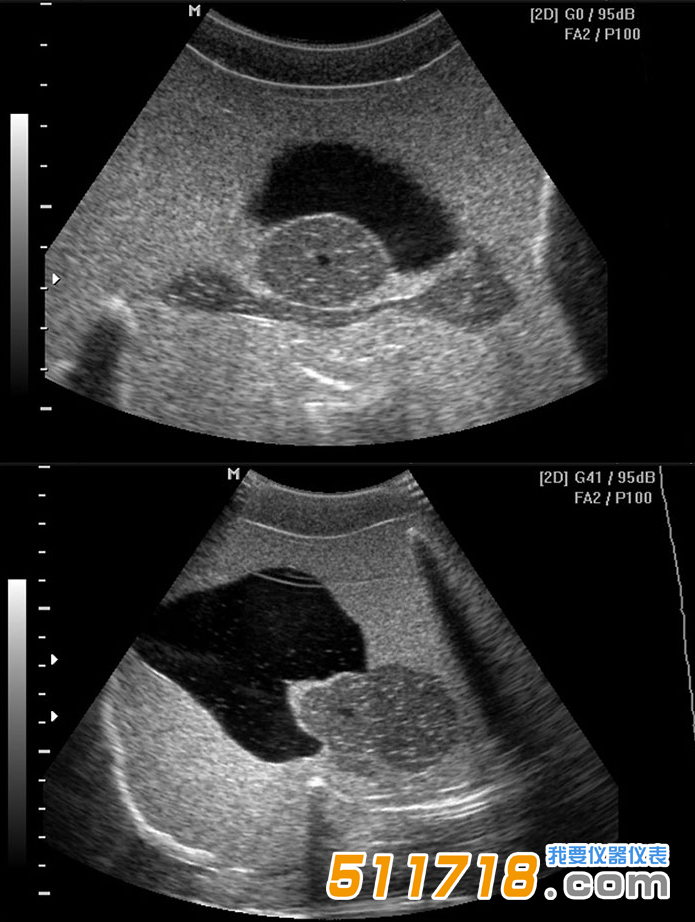

美國(guó)CIRS 048A多模態(tài)男性骨盆模體設(shè)計(jì)用于膀胱和前列腺的真實(shí)腹部和經(jīng)直腸超聲掃描。CIRS

048A多模態(tài)男性骨盆模體包括骨盆骨,消聲性膀胱,前列腺,尿道,精囊和直腸,封閉在帶有Z-Skin?膜的骨盆形塑料外殼中。Z-Skin的自我修復(fù)特性使該設(shè)計(jì)成為活組織檢查和其他圖像引導(dǎo)程序演示的理想選擇。

美國(guó)CIRS

048A多模態(tài)男性骨盆模體由可在超聲,MRI和CT下成像的材料制成,使模體可用于需要多種形式的應(yīng)用,例如放射治療計(jì)劃。該體模具有經(jīng)過(guò)認(rèn)證的前列腺和膀胱體積,可以評(píng)估體積測(cè)量精度。可以進(jìn)行修改,例如*久嵌入式近距離放射治療“虛擬”種子或金基準(zhǔn)標(biāo)記,用于演示目標(biāo)可視化。